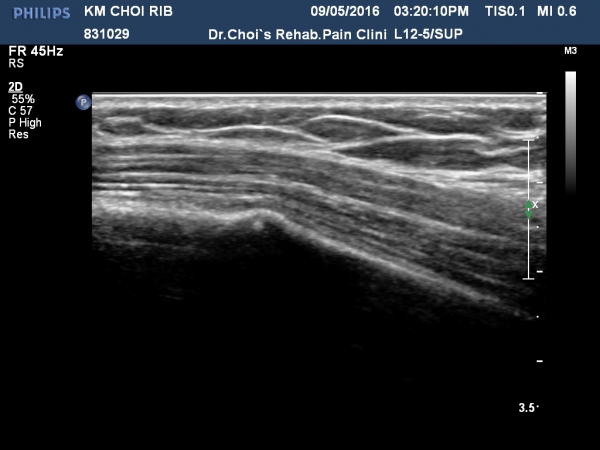

ÃÊÁø ½Ã °¥ºñ»À ÃÊÀ½ÆÄ°Ë»ç¿¡¼­ ÇÇÁú°ñ ¤·³à¼Ó¼º ¼Ò½ÇÀº º¸ÁöÁö ¾ÊÀ¸³ª

±æºñ»À Ç¥Ãþ¿¡ ±¹¼ÒÀûÀÎ ¿¬ºÎÁ¶Á÷ ºÎÁ¾ÀÌ °üÂûµÈ´Ù(»çÁø 1, 2, 3, 4).